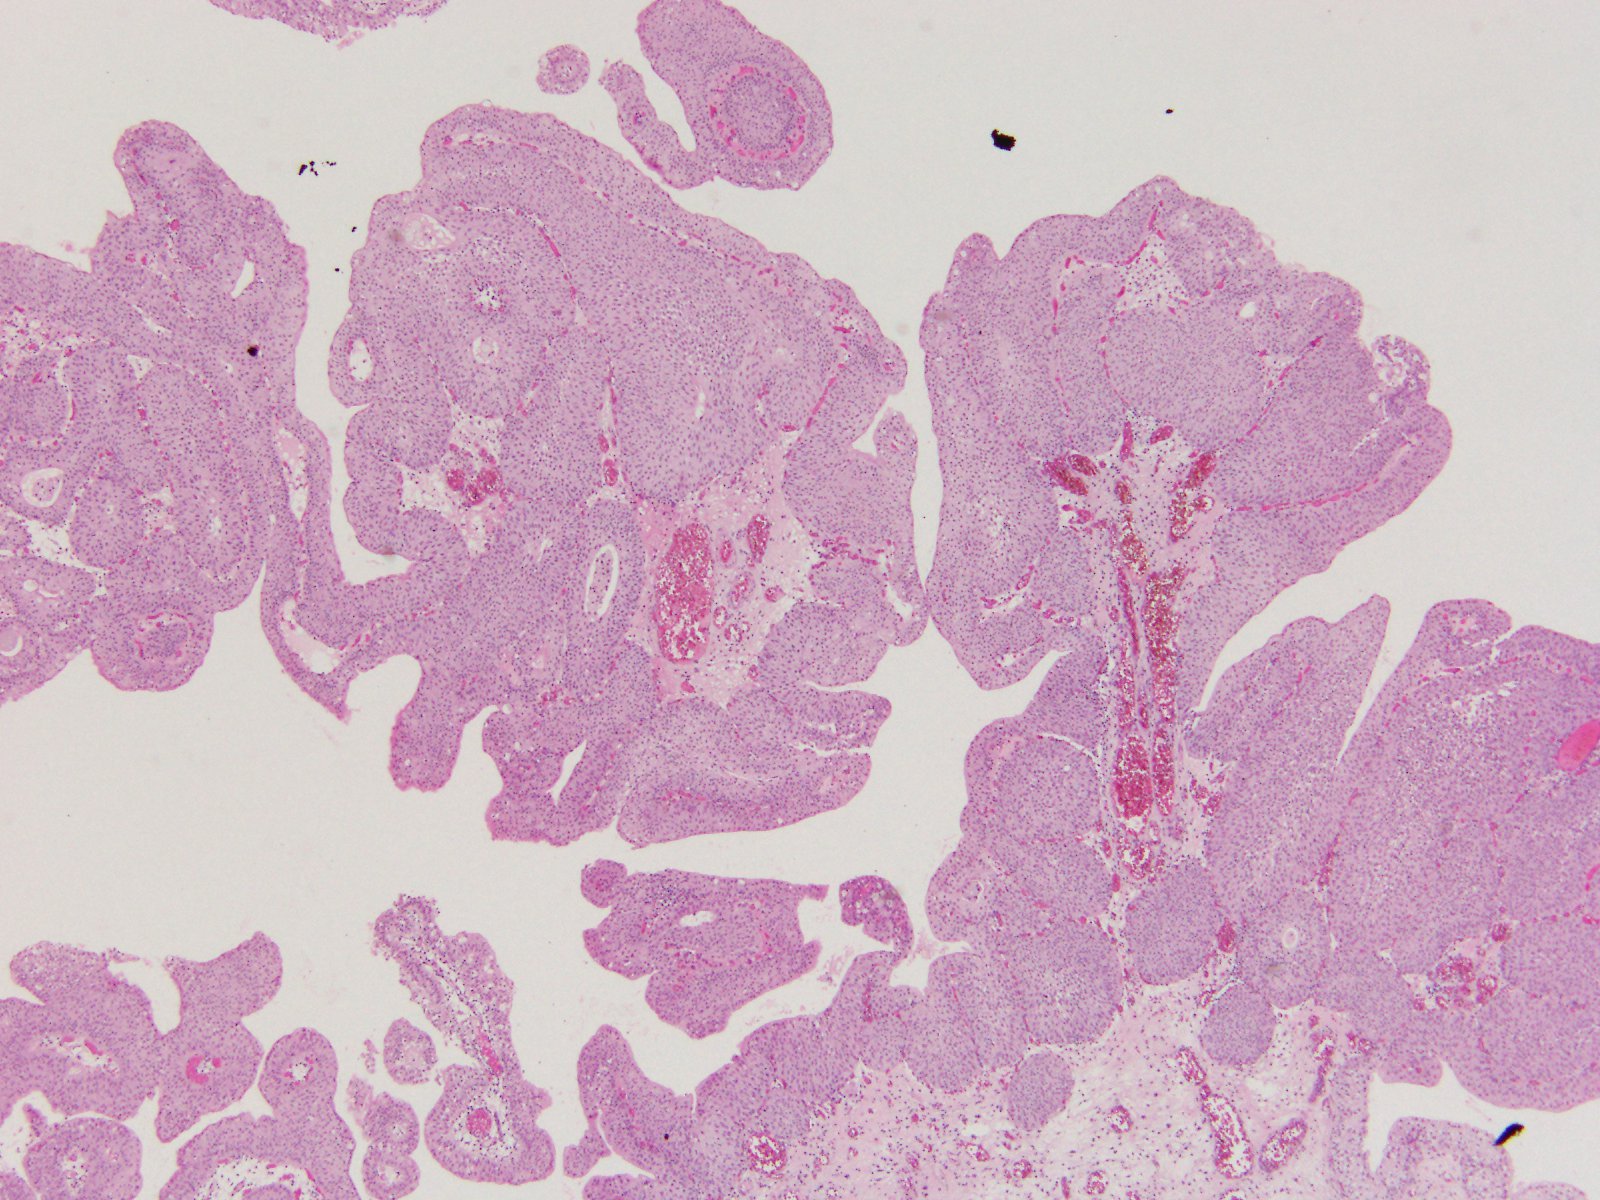

Case ID: 407

Consensus grade: Low-grade papillary urothelial carcinoma (LG-PUC)

Case description (by case creator):

57 y/o. Bladder tumor.